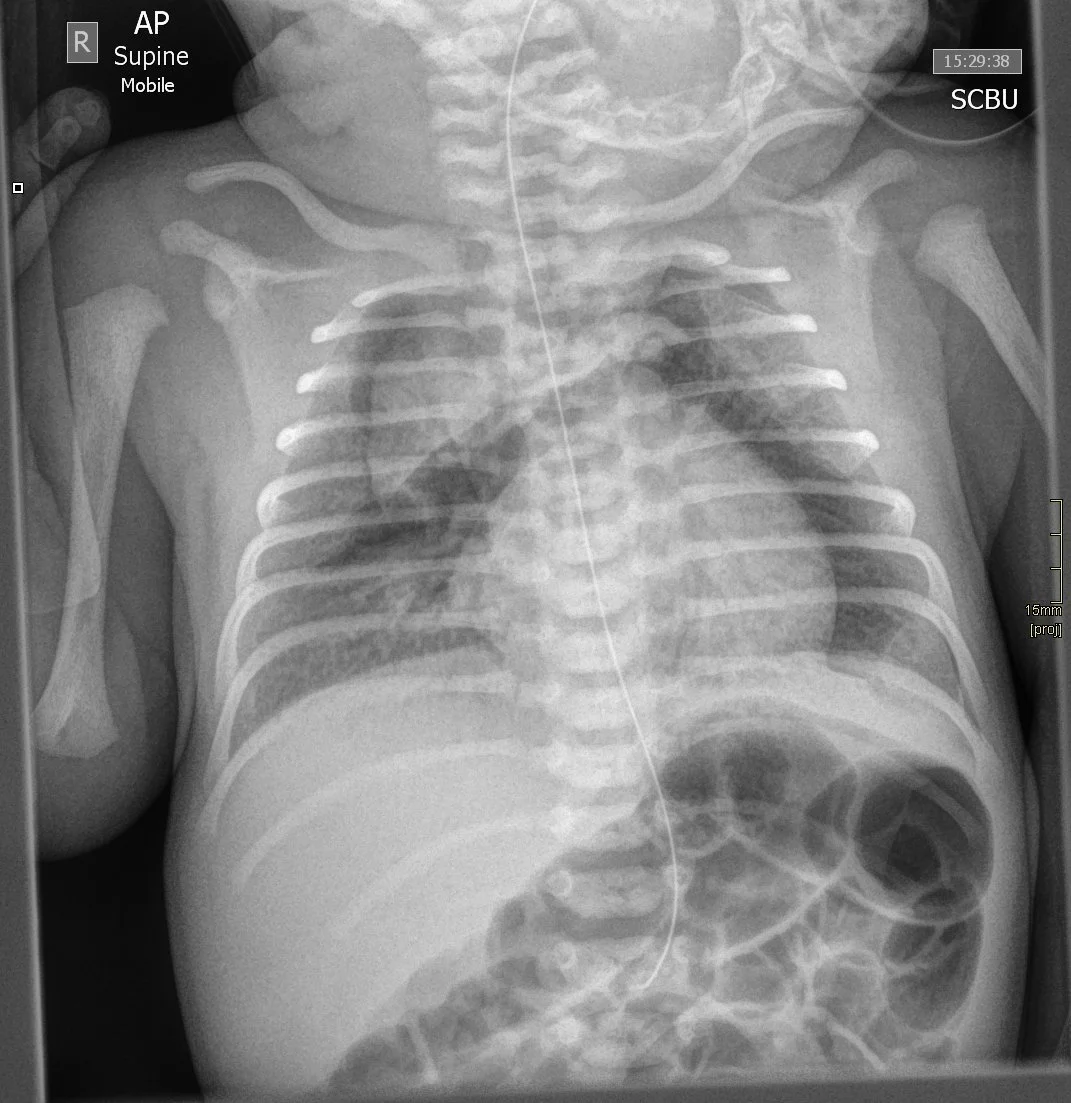

Umbilical Venous line

• Want at IVC-RA junction

• If in RA = not ok

• Abrupt right turn toward liver —> in portal vein

Umbilical Arterial line

• Superior location = T6-T9

• Inferior = L3 ish

• Need away from major branches